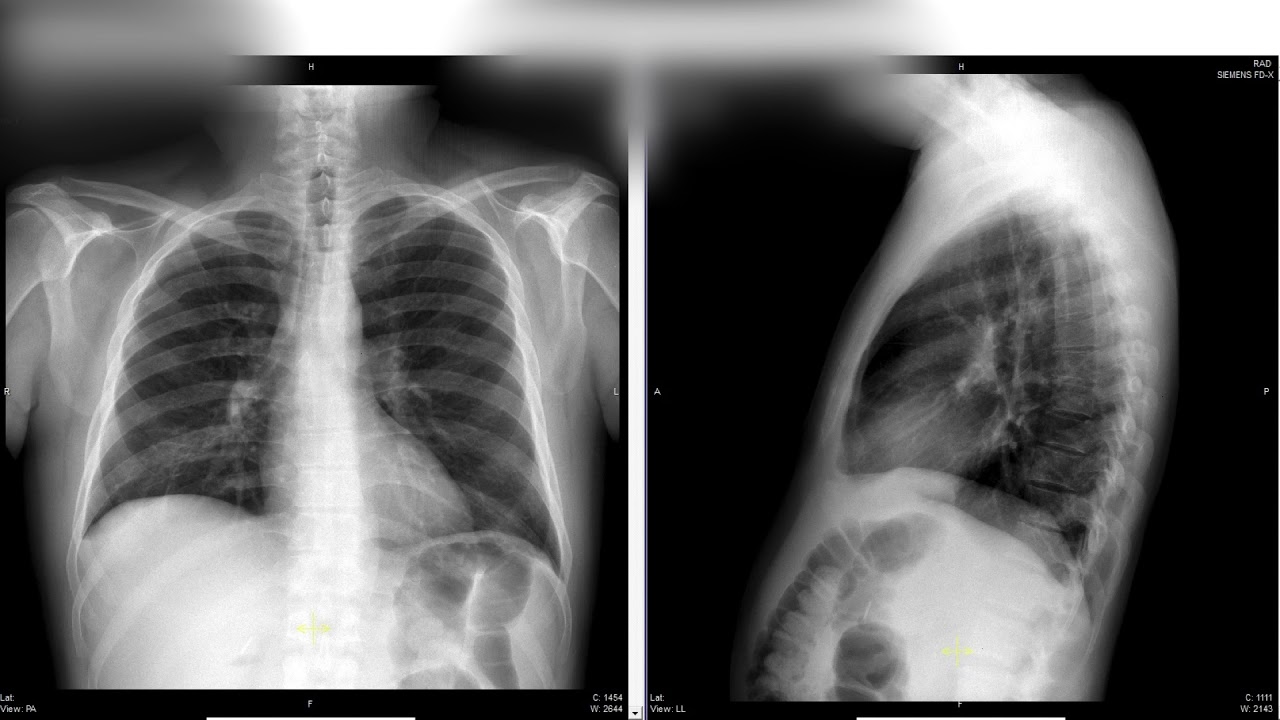

En esta ponencia, el Dr. Richard Chaisson aborda uno de los desafíos más críticos en salud pública: la coinfección VIH y tuberculosis. Su intervención proporciona un análisis profundo sobre:

Panorama actual de la coinfección VIH/TB a nivel mundial y regional.

Diagnóstico y tratamiento integrados, combinando protocolos para ambas enfermedades.